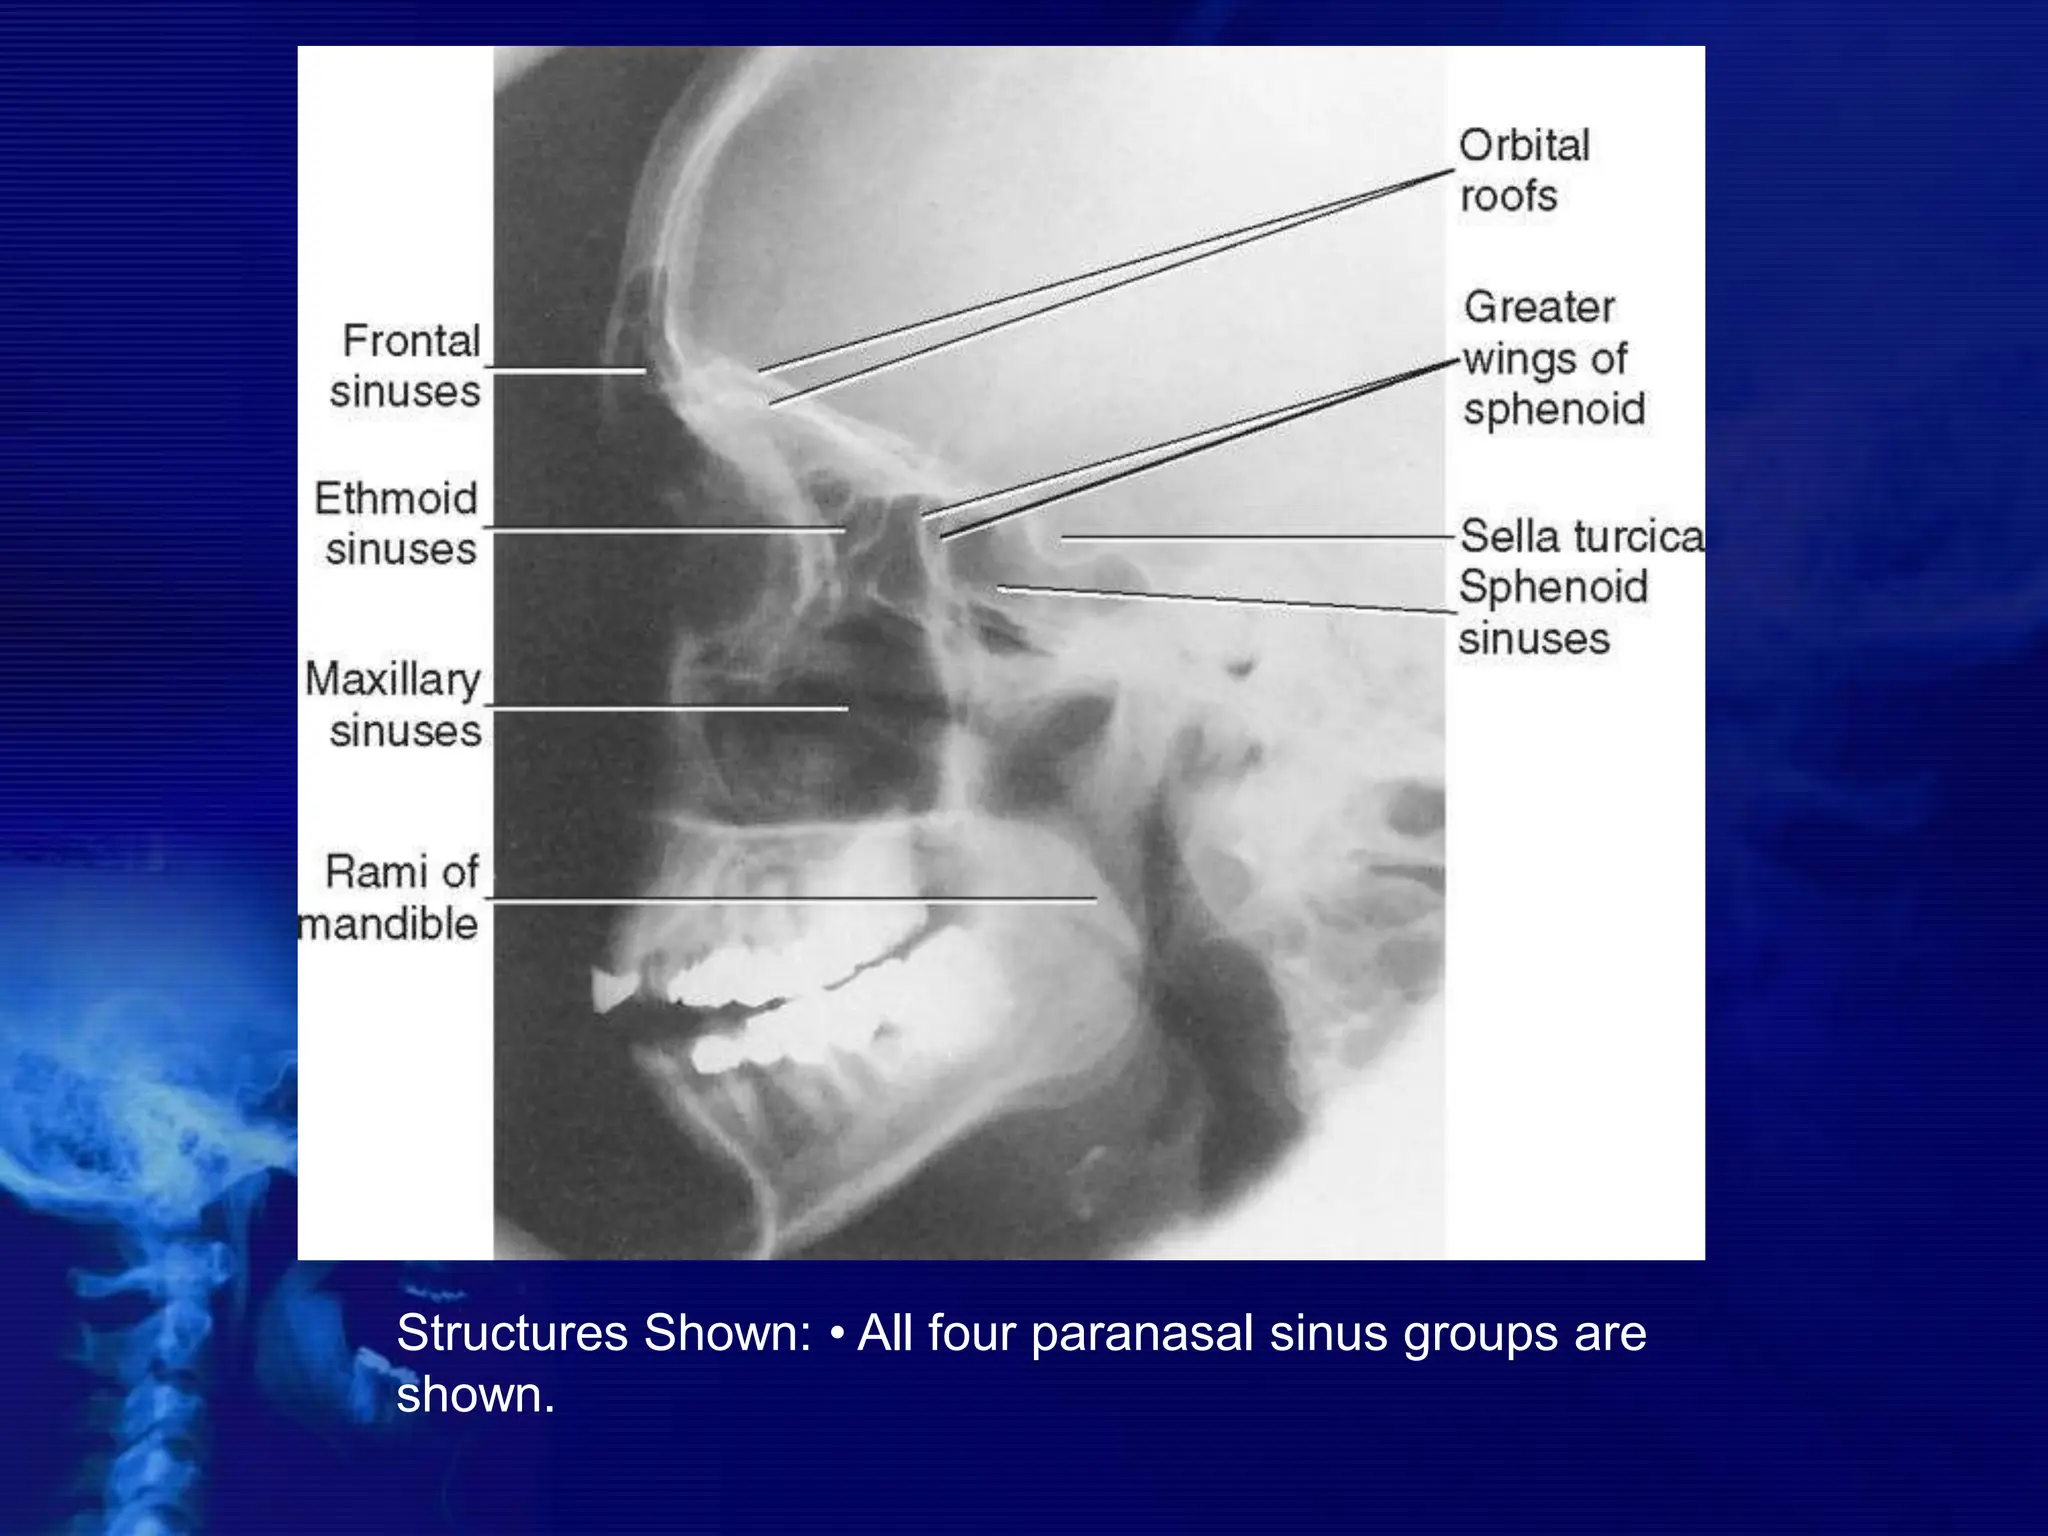

LATERAL VIEW

Lateral side of the skull lies against

the film and x-ray beam is projected

perpendicular from the other side.

Center CR to a point midway between

outer canthus and EAM.

LATERAL POSITION—RIGHT OR LEFT LATERAL: SINUSES

Respiration

Suspend respiration during exposure.

Structures Shown: • All four paranasal sinus groups are

shown.

STRUCTURES SEEN -

 ANTERIOR AND POSTERIOR EXTENT

OF SPHENOID, FRONTAL AND

MAXILLARY SINUSES

 SELLA TURCICA

 ETHMOID SINUSES

 CONDYLE AND NECK OF MANDIBLE